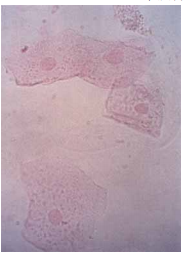

78 圖中為尿沈渣中之何種細胞?

(A)白血球 (B)紅血球 (C)鱗狀上皮細胞 (D)腎小管上皮細胞